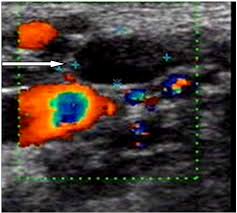

If your cancer diagnosis is based on an ultrasound, it could easily be wrong. But ultrasound is usually the first choice for looking at the thyroid and neck structures. Other causes for a neck mass may be due to cancers such as lymphoma, thyroid or salivary gland cancer, skin cancer, or cancer that has spread from somewhere else in the body. Cancerous lymph nodes can occur anywhere on the neck and are typically described as firm, painless, and sometimes may be immovable. As thyroid cancer gets more advanced, you might notice symptoms like: Cancerous neck masses in adults are most often due to head and neck squamous cell carcinoma (hnscc). An ultrasound of the neck is used to examine the carotid arteries located on each side of a patient's neck. Optimal positioning and exposure of the neck for ultrasound of the thyroid and parathyroid glands (a, b) and lateral neck for lymph node examination and mapping (c).while the vast majority of patients are supine on the exam table with a pillow supporting the shoulders to allow gentle neck extension, keep in mind that some patients have beautiful anatomy (d) that allows ultrasound exam even in. On ultrasound, a breast cancer tumor is often seen as hypoechoic, has irregular borders, and may appear spiculated. And my neck look like an old shapai. The breast tissue kind of looks like waves on the ocean. But now i am worried that the reason the lump didn't show on the ultrasound is because it is actually under the skin in my neck (i.e in my throat) rather than on my actual thyroid/neck. In the framework of such terms as ultrasound of the neck, can be performed the following studies:

If a biopsy is needed, doctors use ultrasound to scan the area again, ensuring that they know exactly where to place the needle. In addition, the following tests may be used to diagnose head and neck cancer: And my neck look like an old shapai. A lump will form when a cancer cell infiltrates the capsule and multiplies. These are frequently seen in nodules containing papillary thyroid cancer. But ultrasound is usually the first choice for looking at the thyroid and neck structures. The normal neck contains scores of lymph nodes some of which are easily seen with ultrasound. Ultrasound an ultrasound is sometimes used, especially to look at the thyroid, salivary glands and lymph glands in the neck.

Ultrasound an ultrasound is sometimes used, especially to look at the thyroid, salivary glands and lymph glands in the neck. The camera remains attached either to a flexible tube called endoscope or to a probe, while it passes within an opening in your body, often your mouth. Fna is generally done on all thyroid nodules that are big enough to be felt. The most common symptom of thyroid cancer is a hard lump on the neck—but most patients experience no symptoms at all. A 'neck check' is a simple procedure that can be done just about anywhere. Doctors and pathologists do not use internal ultrasound scan frequently to detect lymphoma. But i feel great and feel comfortable in my own skin. A small lump on the neck usually is a lymph node, a small sebaceous cyst or a lipoma, although it could be something else. What does a healthy kidney look like on an ultrasound? Thyroid nodules, or lumps, are very common.most aren't cancer. My doctor told me i could hide the scars away, but i don't wanna. And my neck look like an old shapai. Other ultrasound findings that suggest breast cancer include: